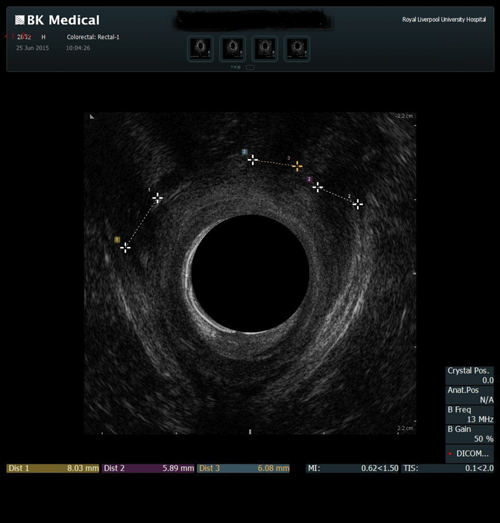

Endoanal ultrasound

This procedure is indicated for assessment of the anal sphincter in patients with incontinence. This allows evaluation of the internal and external anal sphincters (sphincter thickness, length and scarring). It is pertinent to obtain history of obstetric trauma as well as any surgeries / intervention to aid assessment.

As with the proctogram technique, the procedure is explained in detail and consent obtained prior, and the presence of a chaperone makes the patient more comfortable. Digital rectal examination is performed as a reference to assess anal tone. Still images as well as cine of the ultrasound are taken to assess the sphincter complex (Figure 3).

Figure 3a: (Top, middle and bottom) Normal endoanal ultrasound.

Figure 3b: Abnormal / deficient low internal anal sphincter.

Figure 3c: High External anal sphincter scars due to obstetric trauma.